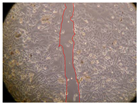

| 2 h | 8 h | 12 h | 24 h | |

| Control | ![]() | ![]() | ![]() | ![]() |

| P. viridis 250 mg/L | ![]() | ![]() | ![]() | ![]() |

| P. viridis 500 mg/L | ![]() | ![]() | ![]() | ![]() |

| B. caapi 250 mg/L | ![]() | ![]() | ![]() | ![]() |

| B. caapi 500 mg/L | ![]() | ![]() | ![]() | ![]() |

| M. hostilis 250 mg/L | ![]() | ![]() | ![]() | ![]() |

| M. hostilis 500 mg/L | ![]() | ![]() | ![]() | ![]() |

| Commercial mixture 250 mg/L | ![]() | ![]() | ![]() | ![]() |

| Commercial mixture 500 mg/L | ![]() | ![]() | ![]() | ![]() |

| P. viridis + B. caapi 250 mg/L | ![]() | ![]() | ![]() | ![]() |

| P. viridis + B. caapi 500 mg/L | ![]() | ![]() | ![]() | ![]() |

| P. viridis + P. harmala 250 mg/L | ![]() | ![]() | ![]() | ![]() |

| P. viridis + P. harmala 500 mg/L | ![]() | ![]() | ![]() | ![]() |

| M. hostilis + B. caapi 250 mg/L | ![]() | ![]() | ![]() | ![]() |

| M. hostilis + B. caapi 500 mg/L | ![]() | ![]() | ![]() | ![]() |

| M. hostilis + P. harmala 250 mg/L | ![]() | ![]() | ![]() | ![]() |

| M. hostilis + P. harmala 500 mg/L | ![]() | ![]() | ![]() | ![]() |